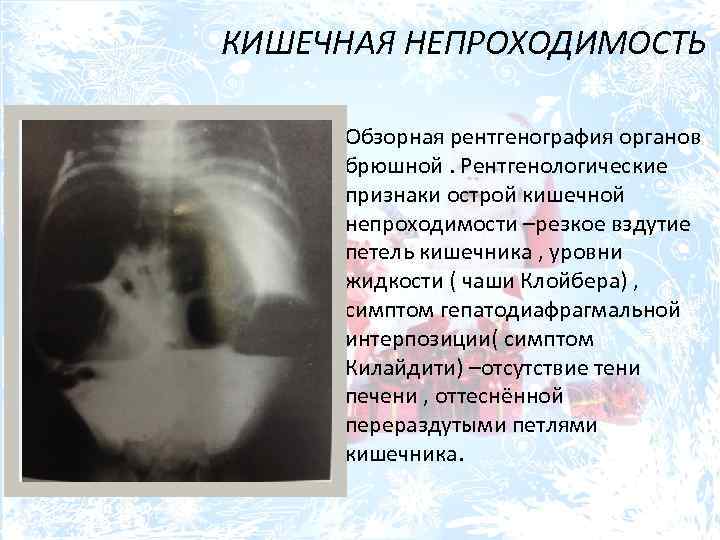

Нормы обзорной рентгенографии брюшной полости